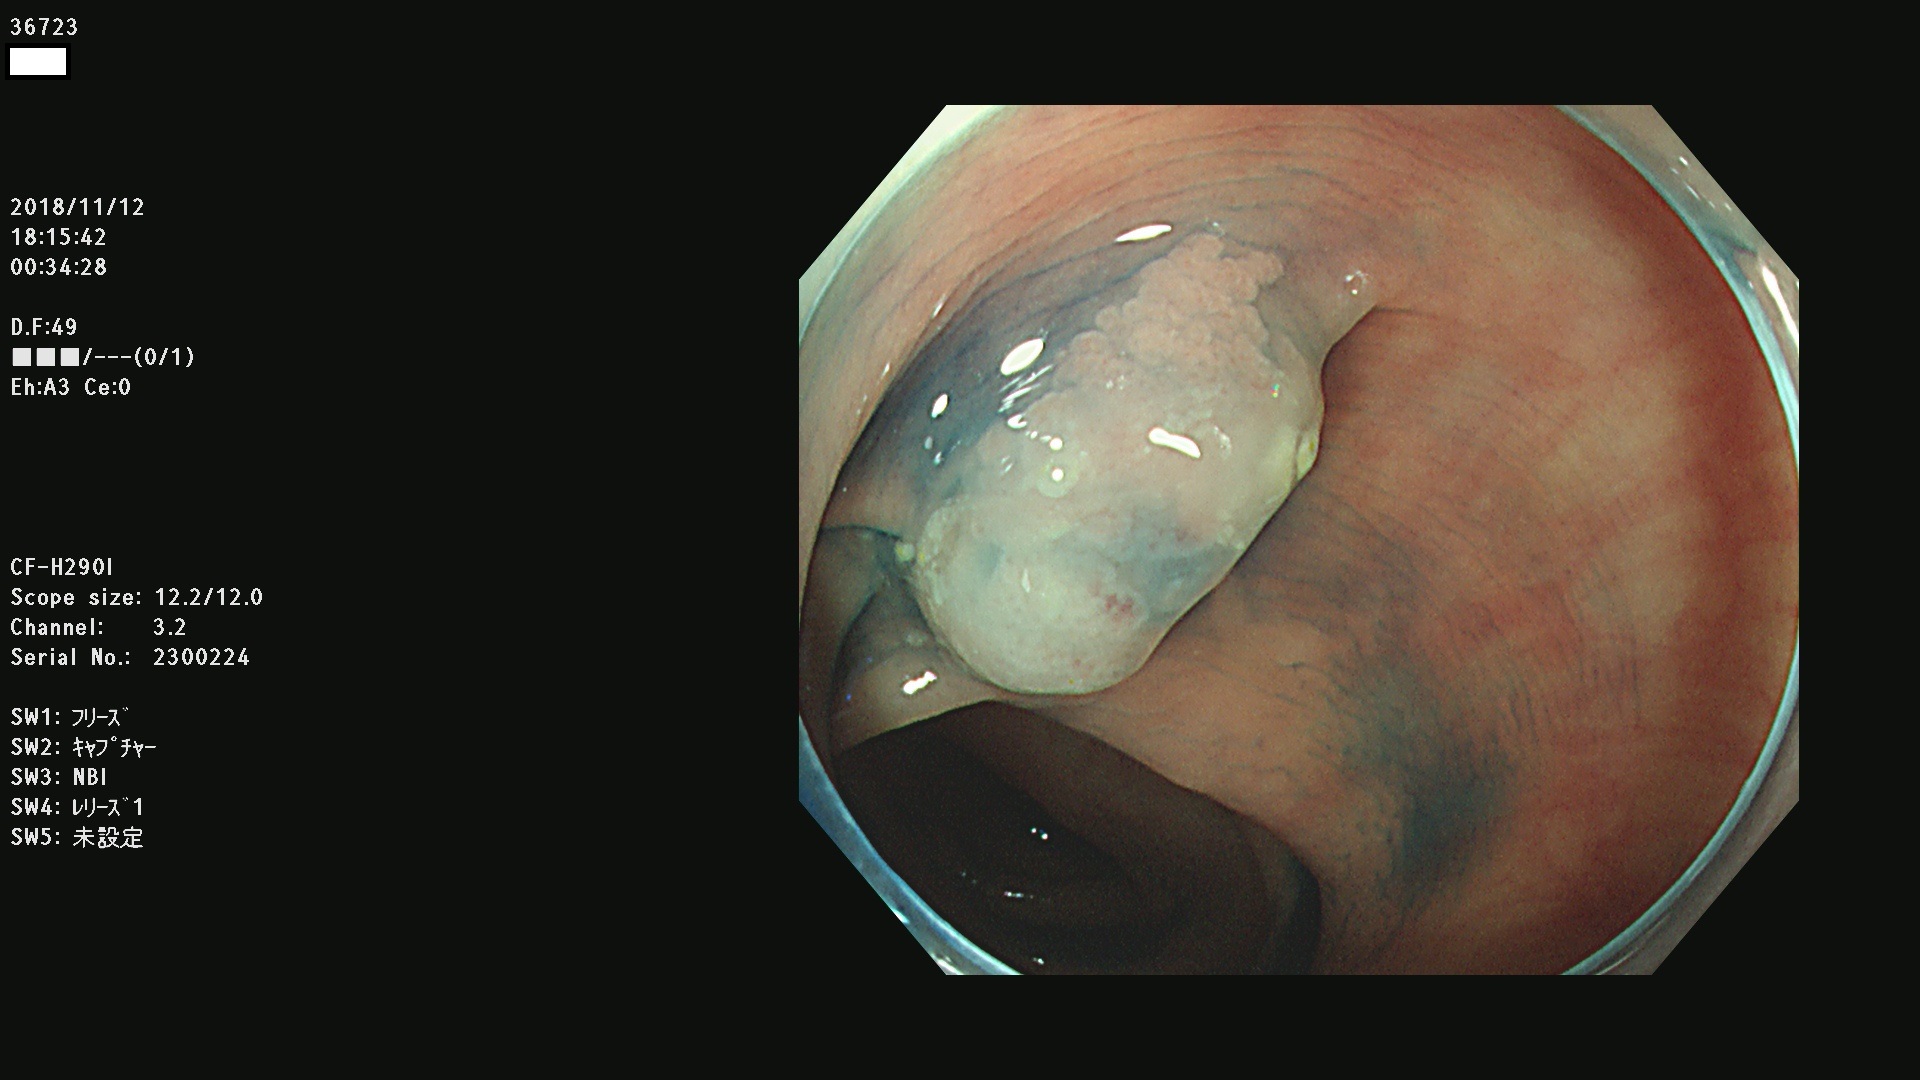

36700 36701 36702 36704 36705 36707 36708 36710 36712(SSAPのみ) 36714 36715 36716 36717 36718 36721 36723 36724 36730 36731 36732 36734 36735 36736 36738 36739 36742 36744 36745 36746 36749 36752(SSAPのみ) 36754 36756 36758 36759 36760 36731 36732 36734 36737 36738 36739 36771(SSAPのみ) 36772 36773 36774 36775 36776 36777 36780 36781 36783 36785 36786 36788 36790 36792 36794 36797 36798

発見困難で危険性の高い平坦型病変(上記100名より抽出)